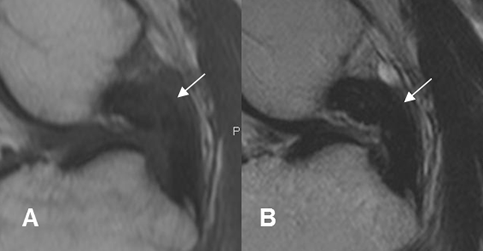

Fig 115. Fibrosis del LCP.

A: RM sagital en T1 y B: RM sagital en T2. El LCP está engrosado y con alteración de la señal, por fibrosis residual.